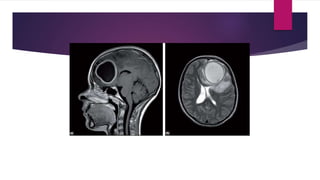

 MRI provides outstanding soft tissue detail without radiation

INTRACRANIAL COMPLICATIONS

 Brain abscess

 complication of either local or distant spread.

 The frontal sinuses are the most common source followed by the ethmoid,

sphenoid and maxillary sinuses.

 Haematogenous spread is the most likely mechanism of distant spread.

 Subdural empyema

 one of the commonest intracranial complications of rhinosinusitis, typically from haematogenous

spread

 Subdural empyemas present with meningeal irritation and neurological signs such as seizures or

focal deficits.

 Serious neurological injury can occur if not treated rapidly and aggressively with combined

treatment and neurosurgical drainage to decompress the brain and evacuate the empyema.

 Investigations

 MRI scanning has been shown to be superior to CT in the diagnosis of

complications and is the investigation of choice for the diagnosis of suspected

intracranial extension.